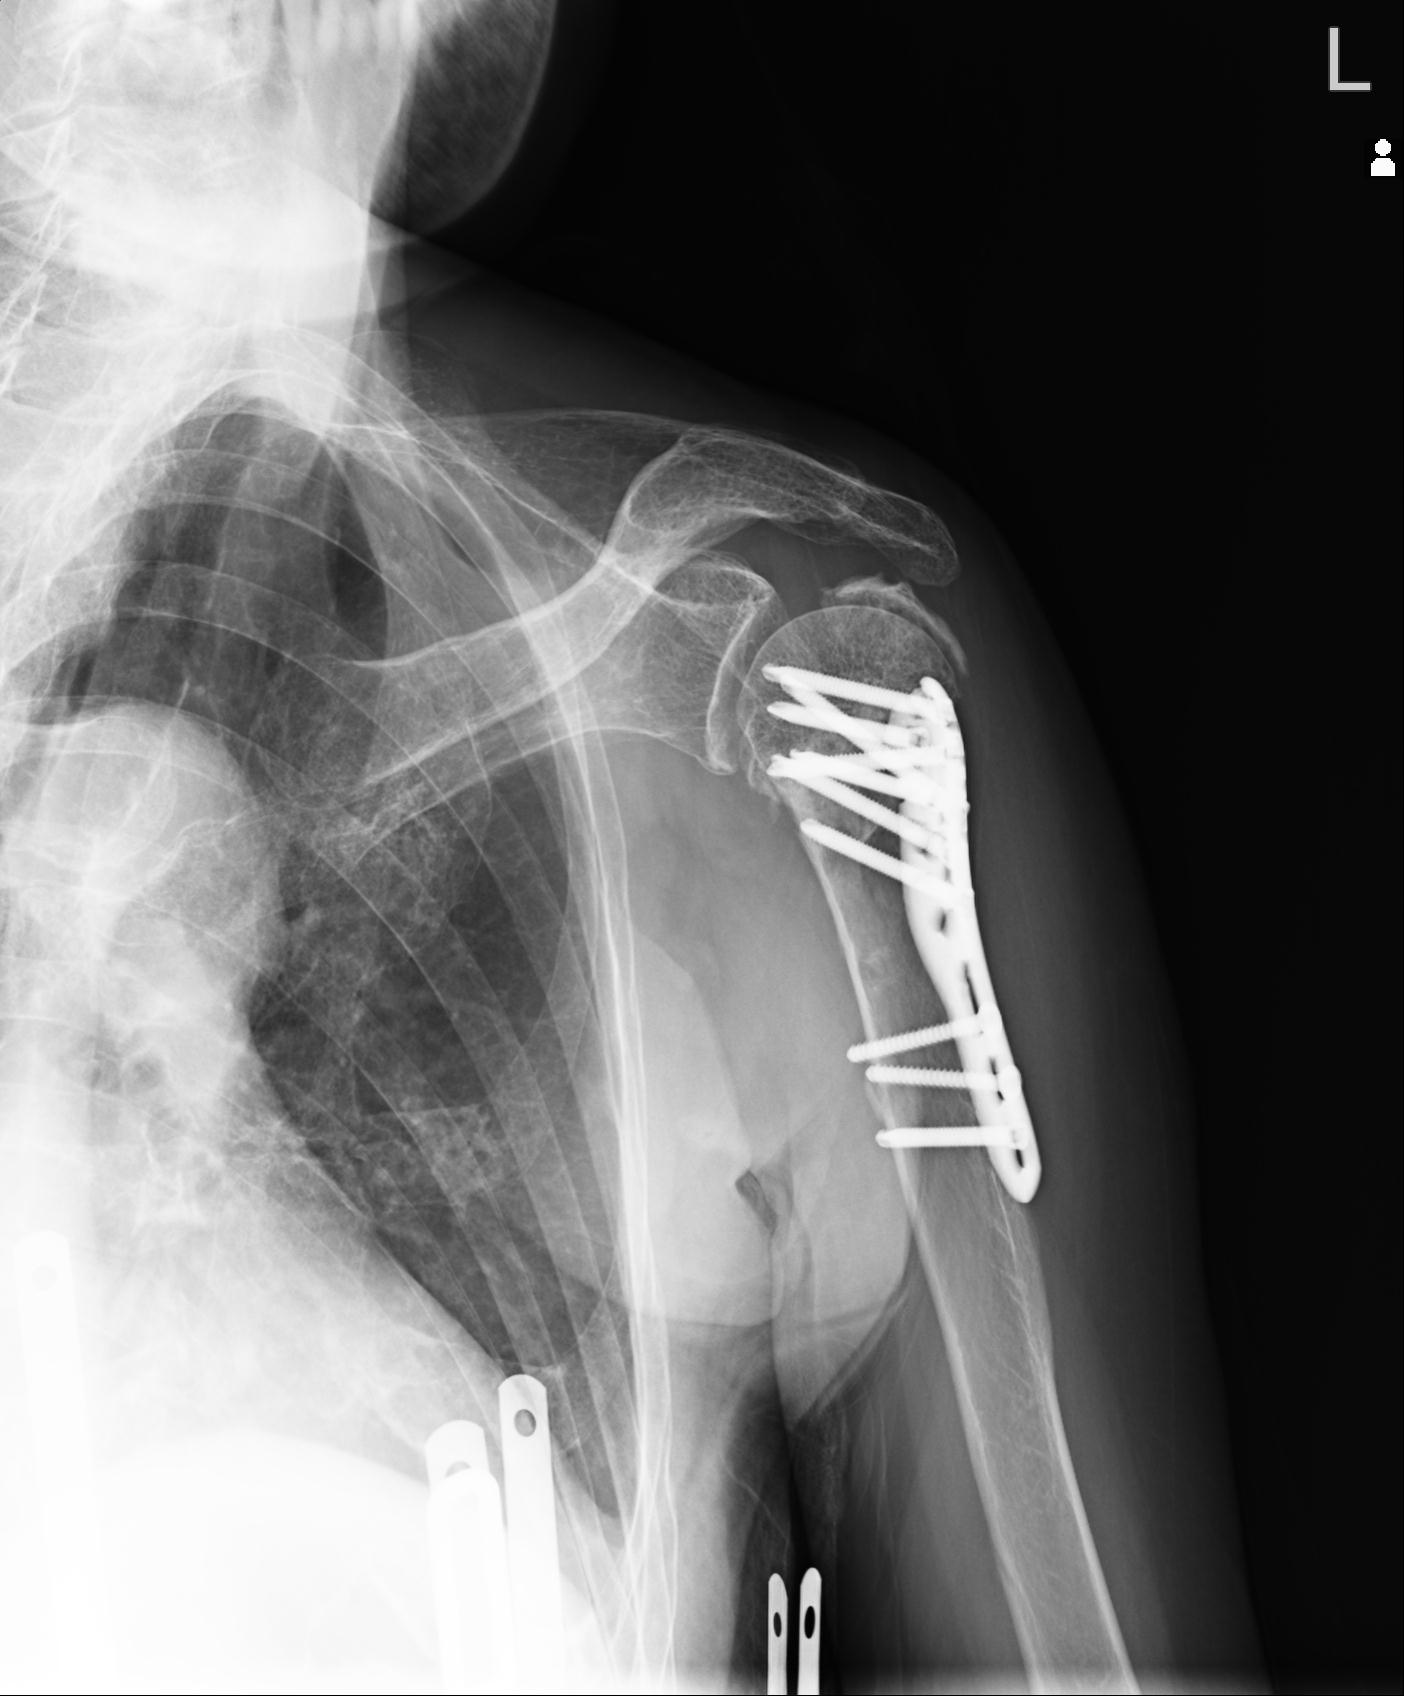

110214 12/20 肩 2R 12/21 肩 4R 72歳女性 左上腕外科頚プレート